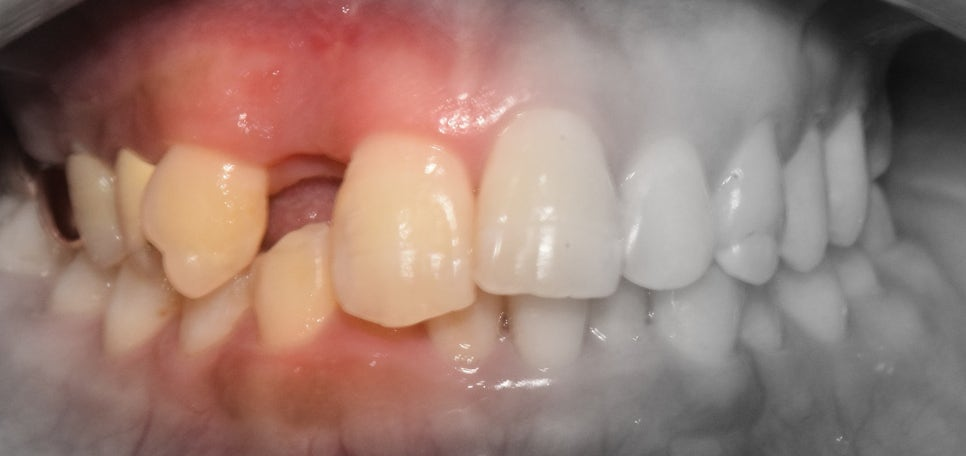

앞니가 빠졌어요! 어쩌죠? 이럴 때는 조금 침착하게 생각을 해야 됩니다. 먼저 가까운 치과에 하루 빨리 내원을 하셔서 현 상황을 정확하게

어금니쪽과 다르게 앞니 쪽에는 치아 뿌리를 감싸고 있는 치조골의 폭경이 좁습니다. 즉, 추후 임플란트 를 심으려 했을 때 충분한